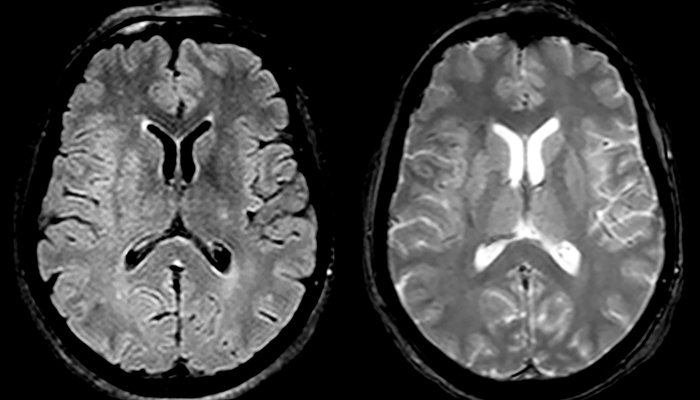

Multiple sclerosis imaging requires precision, speed

When multiple sclerosis (MS) is suspected, clinicians need a diagnosis early on, so treatment can begin as soon as possible. “A challenge for imaging is that MS lesions in the brain and spine may be very small,” says Dr. Savatovsky. “We need precise imaging to tell exactly where the lesion is, so we need high quality, very high resolution images, preferably in 3D[1]. We need to know if a high T2 signal intensity is suggestive of MS or just aspecific. And we want to visualize active lesions very well.”

“Ingenia 3.0T provides us very good image quality with high SNR, even if we push the resolution. For example, in FLAIR images we may have an isotropic resolution of 0.9 mm. Ingenia allows us to use 3D T1 TSE with BrainView, which has a better sensitivity than 2D spin echo imaging[2] and 3D gradient echo imaging. Ingenia also provides highly reproducible exams, which is important in MS imaging so that follow-up exams at different time points are done the same way.”

Imaging MS in brain

For MS imaging in the brain, Dr. Savatovsky uses 3D FLAIR as the basic sequence to visualize the lesions and assess the situation and lesion load. “We count the lesions in each location to determine if the criteria of the disease are fulfilled. We use a T2-weighted sequence because our neurologists are used to it. We compare the lesion load on FLAIR with a 3D T1 post-contrast sequence to help us determine whether lesions are old or new. We typically administer the contrast before the patient enters the machine because it shortens the examination time and allows to visualize active lesions that tend to be more visible after several minutes. When a differential diagnosis is difficult, we add sequences such as susceptibility imaging, because some focal MS lesions have a small vein in the center[3].”